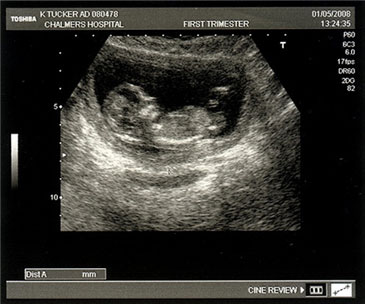

Well it's been nearly two years since I last posted here, and guess what? Kerry, Mylo and I will be joined in November by another little Turnbull!

Here’s the first ever picture.